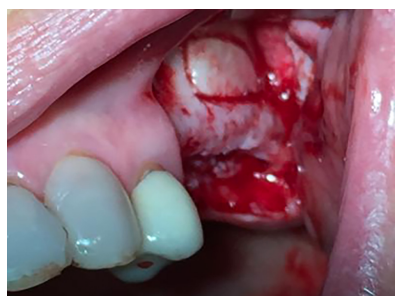

El abordaje quirúrgico fue realizado mediante una incisión lineal crestal y dos descargas verticales, mesial y distal, procediendo al despegamiento mucoperióstico para la obtención de un campo quirúrgico adecuado. Se realizó el diseño de una ventana lateral con piezoeléctrico (VarioSurgery®) (Figura 4), despegándose a continuación la membrana sinusal sin perforación alguna (Figura 5). A continuación, se procedió al relleno mediante un compuesto de fosfato de calcio-potasio-sodio bioactivo (Osseolive®) (Figura 6), acompañado de la colocación de una membrana de ácido poliláctico (EPI-Guide®) (Figuras 7 y 8), finalizando la intervención con la reposición del colgajo mucoperióstico y sutura con poliamida de 4/0 (Supramid®) (Figura 9).